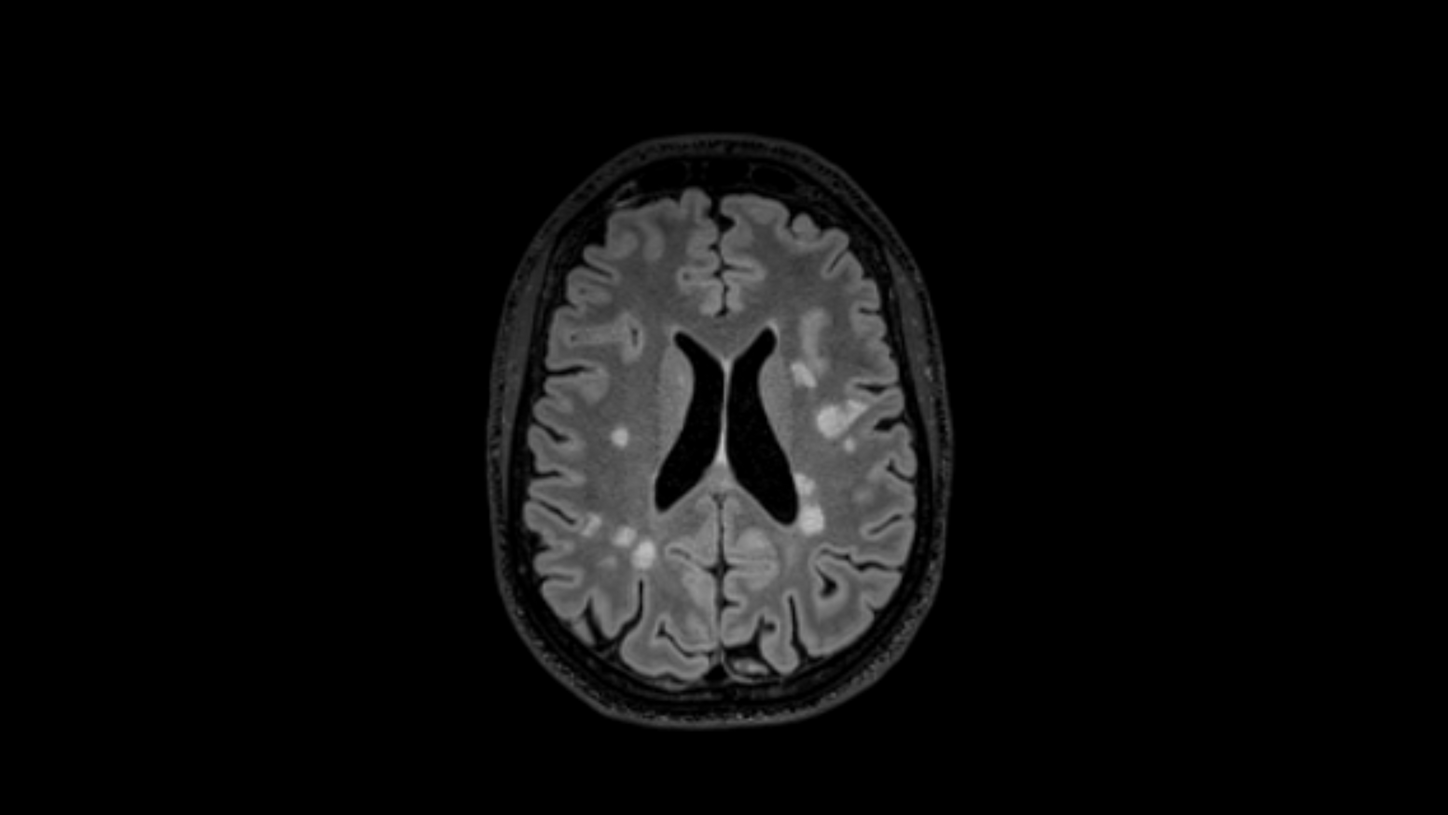

White Matter Hyperintensities (WMH)

As an autoimmune disease, MS is characterized by an overactive immune system, resulting in inflammation areas that lead to the loss of myelin insulation of nerve cells. These active inflammation areas can be seen in MRI on T2-weighted TSE imaging, primarily in the T2 FLAIR contrast. They manifest as hyperintensities, meaning areas with enhanced brightness. As MS patients undergo regular MRI scans to follow-up the disease, these lesions appear at different spatial locations in the brain (dissemination in space, see below). However, as a confounder, such hyperintense areas do not only result from MS, but also from other root causes and sometimes require additional contrasts (e.g., MPRAGE or T2*/SWI) to rule out differential diagnoses.

Dissemination in space (DIS)

DIS refers to the development of lesions in distinct anatomical locations within the central nervous system (CNS): intra- or juxtacortical, periventricular, infratentorial, and spinal cord. The 2024 McDonald criteria2 added the optic nerve to these anatomical locations. If MS lesions appear in at least two anatomical locations, DIS has been demonstrated. This acknowledges the multifocal process which is characteristic for MS.